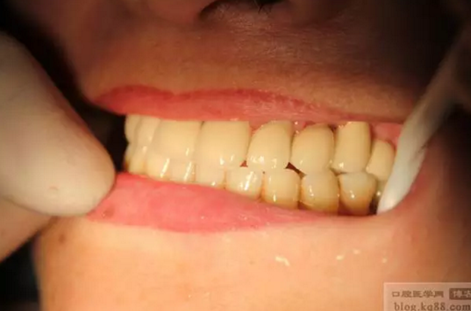

上前牙做充填和纖維樁修復(fù)后左上后牙內(nèi)提升植入三顆植體